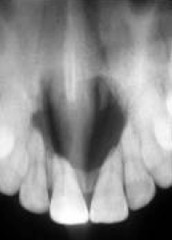

nasopalatine canal cyst

-40-60yr men>women -asymptomatic pink bulge at the incisive papillae area well circumscribed radiolucency between the maxillary central incisors -HEART SHAPED